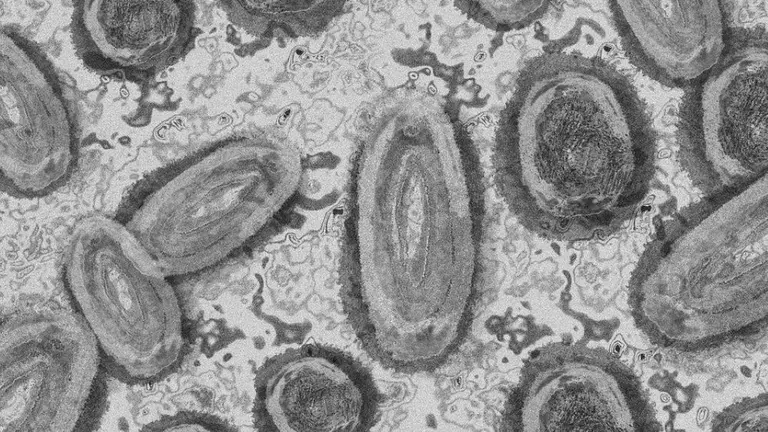

Canarias recibe 273.600 dosis de las vacunas contra la covid adaptadas a las variantes de Omicron Las nuevas vacunas comenzarán a inocularse el próximo lunes 26 de septiembre y la población diana, la mayor de 80 años, será citada por su centro de… biosferamedia